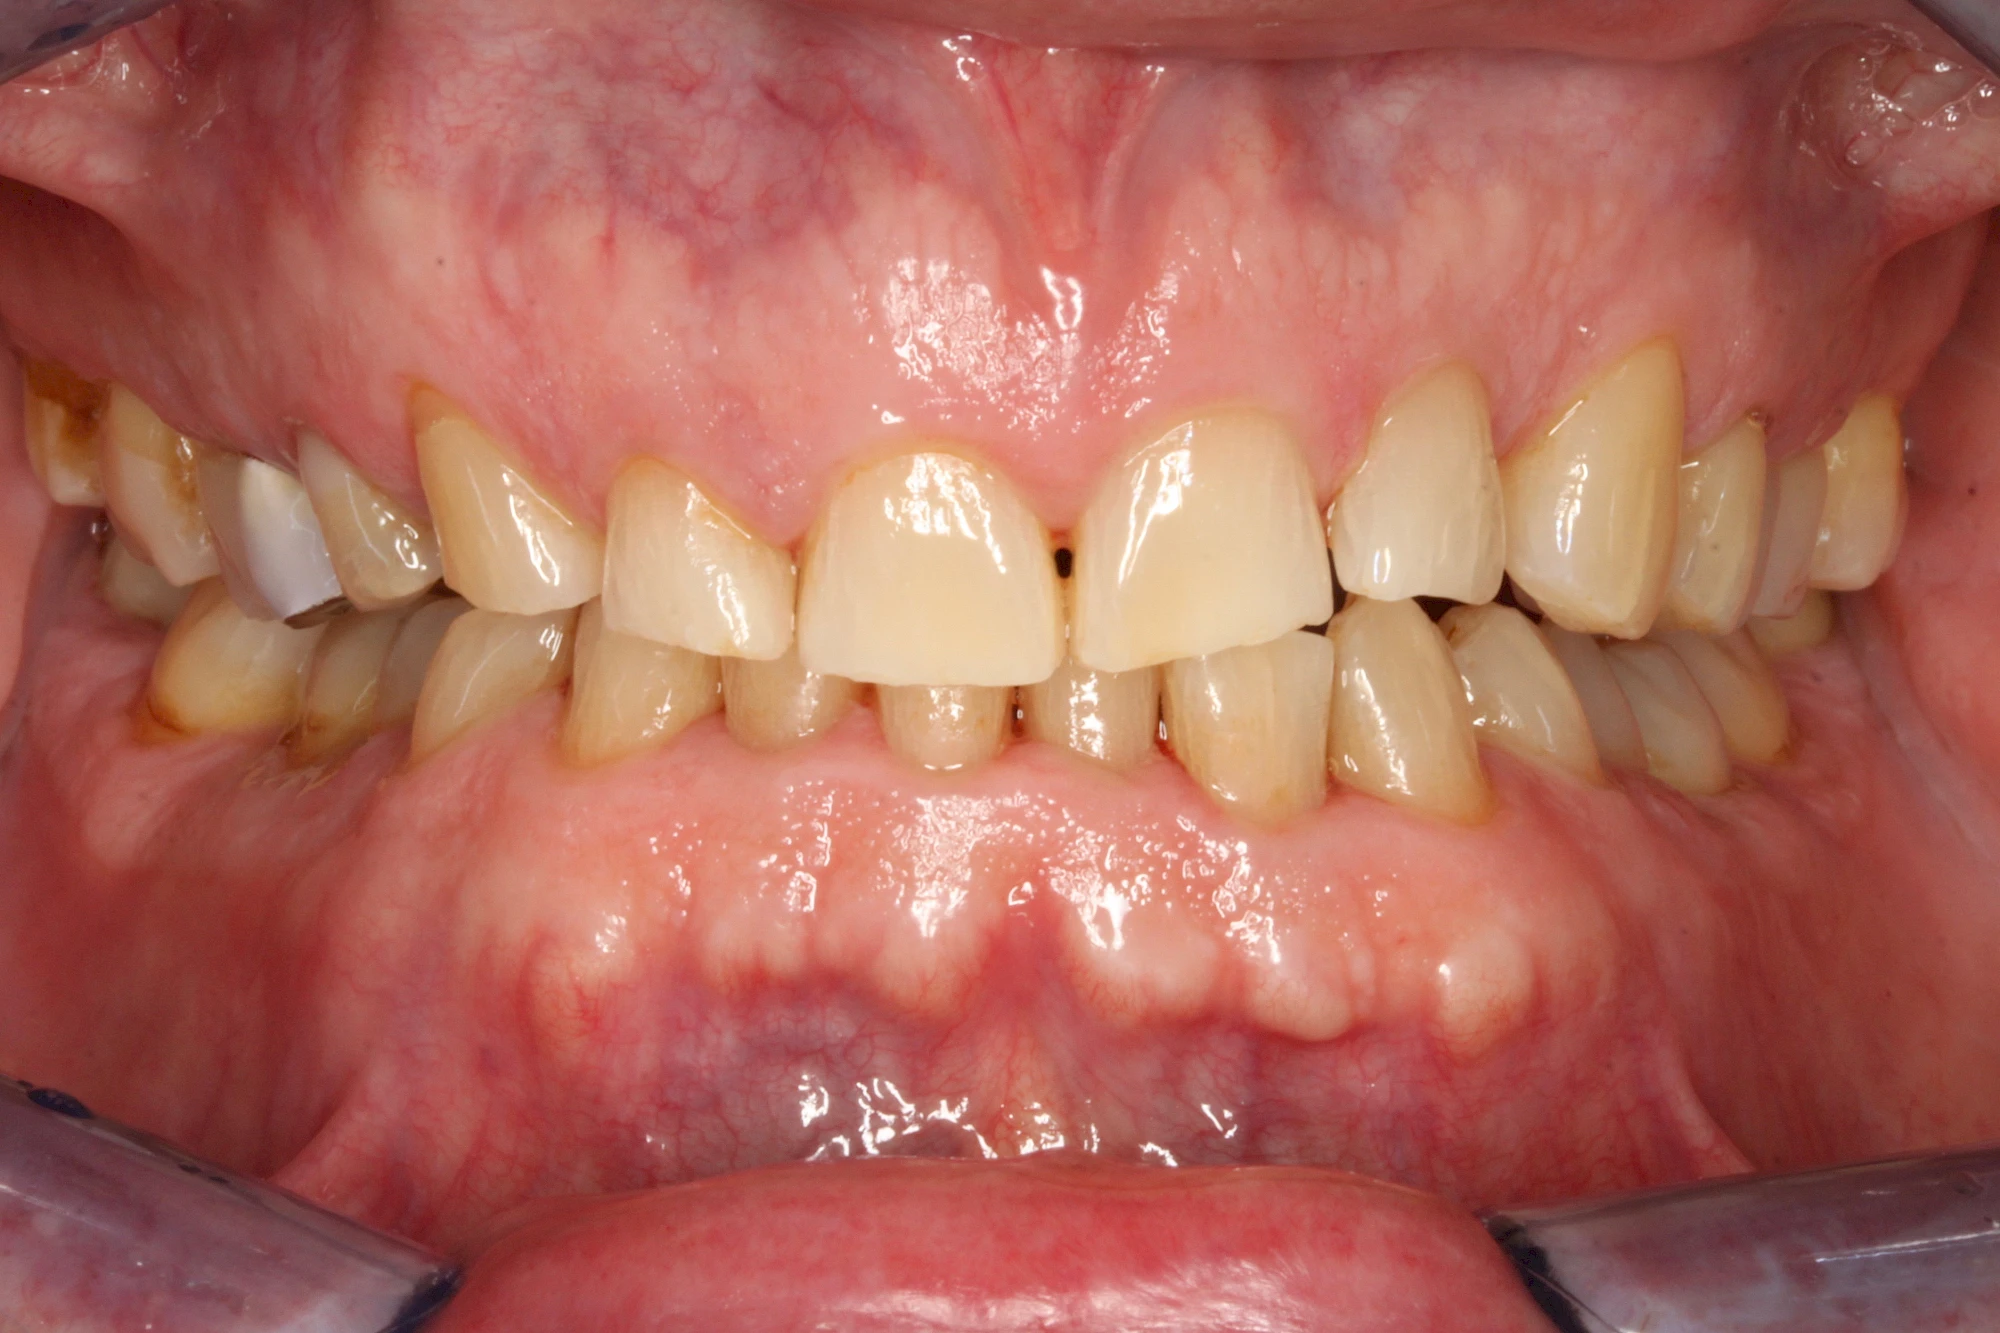

Über die Zeit können verschiedene Prozesse die Zahnhartsubstanzen aufzehren:

- Abnutzung durch Kauen (Abrasion) oder duch durch übermäßiges Knirschen bzw. Pressen (Attrition)

- Säurebedingte Auswaschung (Erosion)

- Knirschen bzw. Pressen und ungünstige Putztechnik (Druck): keilförmige Defekte

Auswaschung (Erosion) dagegen ist eine Verschleißerscheinung der Zähne aufgrund von immer wiederkehrenden Säureangriffen durch die Nahrung, verstärkt zum Beispiel durch den Genuss säurehaltiger Getränke oder Speisen. Auch bei Menschen mit einer Essstörung (z. B. Bulimie) können die Zähne durch die Magensäure ausgewaschen erscheinen.